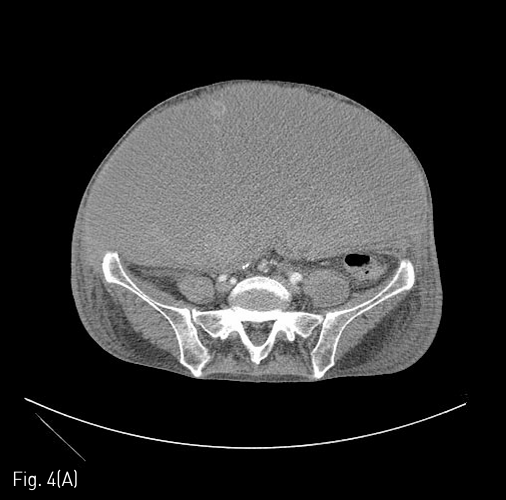

Fig 4A

(A) 4 days later, the size of the abdominal wall hematoma was more increased (about 31 x 15cm), and posterior displacement of the visceral organs was noted on follow-up abdomen CT.

Fig 4B

(B) Another active bleeding focus was detected at left lower abdominal wall near by the left suprapubic inguinal area.